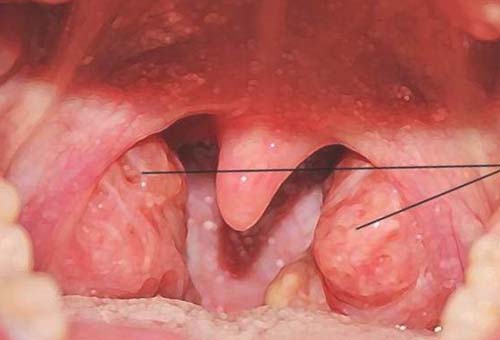

- Узелки голосовых складок («узелки певцов»). Небольшие доброкачественные образования, возникающие из-за хронической голосовой перегрузки, которые делают голос сиплым и грубым.

- Полипы голосовых складок. Обычно односторонние образования, которые могут иметь разную форму и размер, приводящие к выраженной охриплости.

- Кисты голосовых складок. Замкнутые полости с жидким или полужидким содержимым, которые нарушают вибрацию складки и вызывают стойкое изменение голоса.

- Отек Рейнке. Диффузный отек голосовых складок, чаще всего связанный с курением, который приводит к значительному понижению и огрубению голоса, особенно у женщин.

- Гранулемы. Доброкачественные образования, часто возникающие в задних отделах гортани из-за травмы (например, после интубации) или гастроэзофагеального рефлюкса.

- Папилломатоз гортани. Заболевание, вызванное вирусом папилломы человека (ВПЧ), характеризующееся ростом множественных новообразований, которые могут нарушать не только голос, но и дыхание.

- Рубцовые изменения и борозды голосовых складок. Состояния, при которых нарушается нормальная структура слизистой оболочки, что мешает ее волнообразным движениям и приводит к слабому, придыхательному голосу.